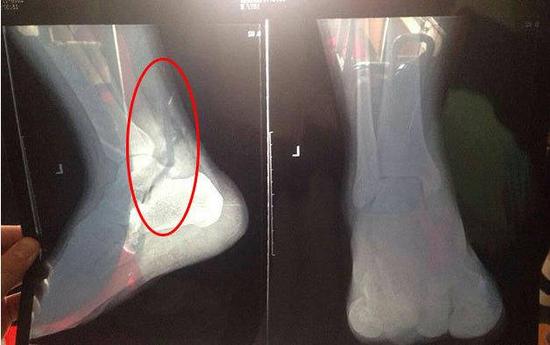

11月17日,梁小胖在宿舍休息,左脚的同一个位置突然剧烈发疼,“疼到走路都走不了了!”梁小胖同学马上让舍友搀扶着打车去医院。经检查,医生称梁小胖左侧距骨内侧缘撕脱性骨折,“要包两个星期纱布!”第二天,梁小胖的左脚开始肿胀,他开玩笑说“肿得跟猪蹄一样啦!”

梁小胖同学拍的片子